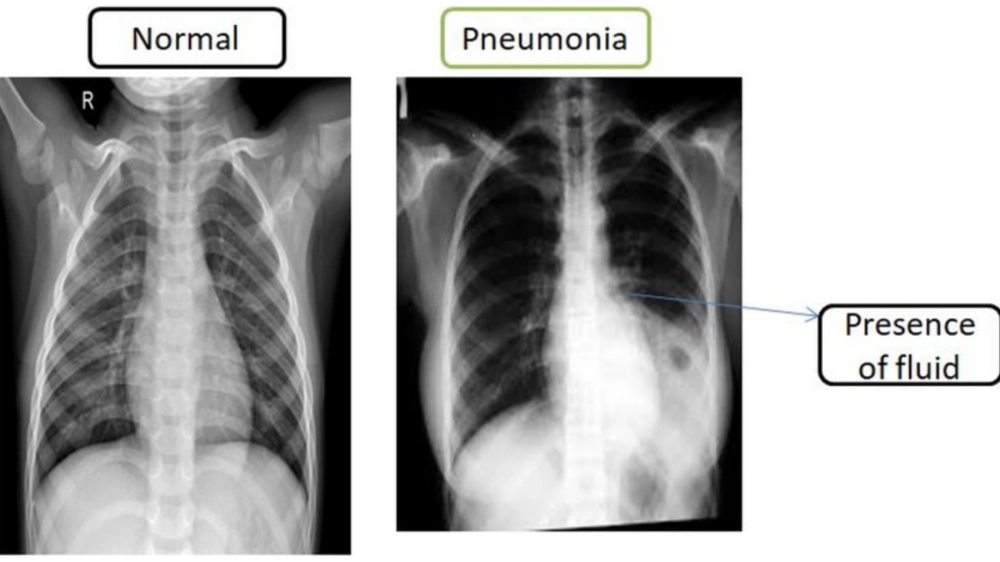

Hình ảnh chụp X-quang phổi của bệnh nhân bị viêm phổi